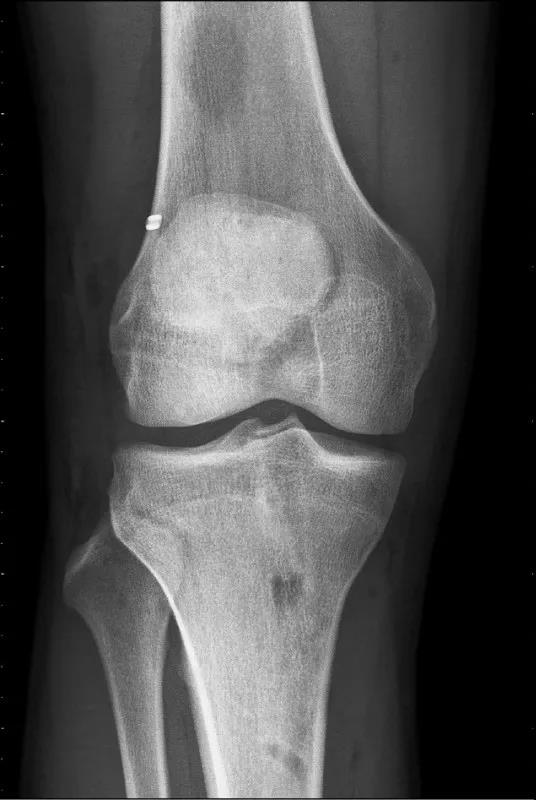

前十字韧带重建合并外侧肌腱固定术后X光